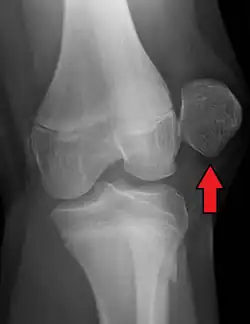

| X-ray showing a patellar dislocation, with the patella out to the side. | |

A patellar dislocation is a knee injury in which the patella (kneecap) slips out of its normal position.[5] Often the knee is partly bent, painful and swollen.[1][2] The patella is also often felt and seen out of place.[1] Complications may include a patella fracture or arthritis.[3]

Displacement of the patella laterally out of its groove strains the medial stabilizing connective tissues, particularly the medial patellofemoral ligament (supporting 50–80% of the knee mechanisms in lateral patellar glide), which is torn usually at its femoral attachment.[3] Traumatic patellar dislocation may cause bleeding into the joint space, ligament and muscle attachment tearing, and fracture of the medial wing of the patella.[3] Fracture of the weight-bearing portion of the lateral femoral condyle occurs in 25% of traumatic patellar dislocations.[3] Surgical repair of the patellar stabilizing structures – the medial patellofemoral ligament and vastus medialis muscle – may be needed for athletes.[3]